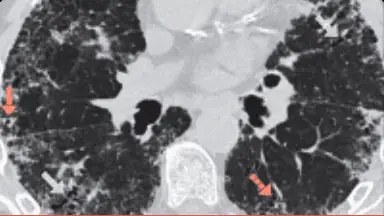

PH, pneumonită de hipersensibilitate; HRCT, tomografie computerizată de înaltă rezoluție; PID, pneumopatie interstițială difuză.